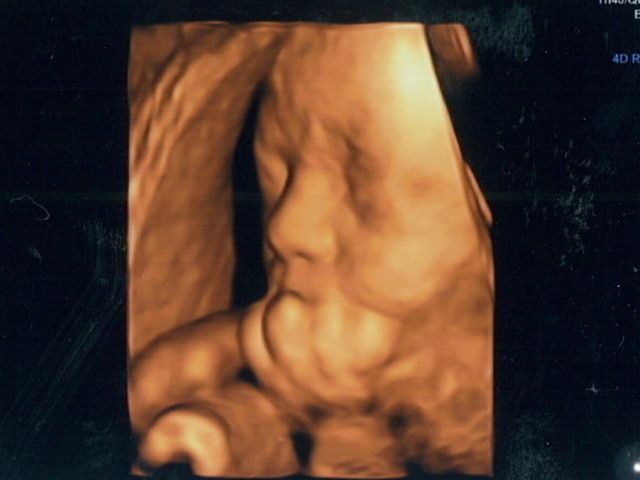

立体的な画像が動く!4D超音波

「4D超音波は、3次元(①縦軸②横軸③奥行軸)にプラスもう1次元(④時間軸)の情報を組み立てるので、立体的な画像が、動画のムービー状態で見られるもの。おなかの中で赤ちゃんが頭をかいたり、指をちゅぱちゅぱ吸ったりしている、かわいい様子をリアルに見ることができます。実際に見ると、『赤ちゃんがますます愛しくなった♡』というママとパパがとても多い! 医学的な意味だけでなく、親子の絆づくりにも高い効果が望める検査といえるでしょう」